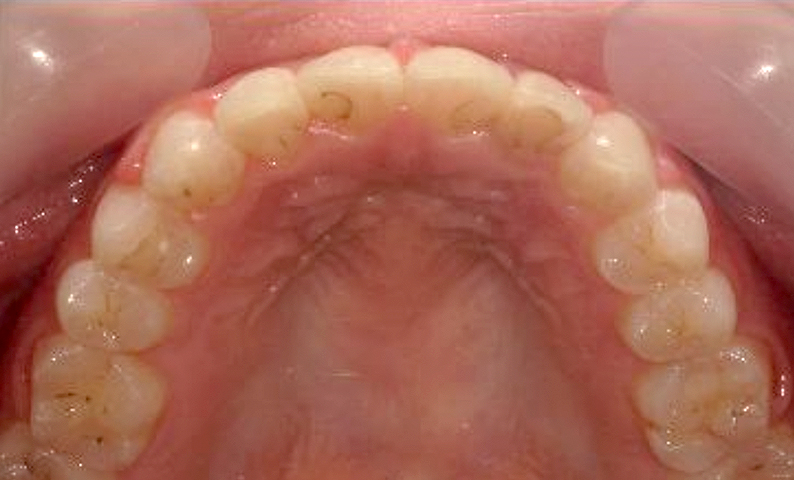

症例_025 上下顎の部分矯正

治療期間:13ヶ月金額:51万円+税女性前歯のガタガタ出っ歯

| Before | After |

|---|---|